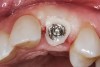

The cast used to fabricate the provisional as described above will work if the provisional was not altered. If it was altered, the screw-retained provisional is placed onto an analog and the analog is partially embedded in stone. (The clinician can stock a few embedded implant analogs of various sizes to expedite this process for future cases.) VPS bite registration material is then injected around the provisional covering the analog. Once set, the provisional is unscrewed, and a direct (open tray) transfer coping placed on the analog. Then, pattern resin (eg, GC Pattern Resin™, GC America, www.gcamerica.com) or flowable composite is flowed around the transfer coping, duplicating the cervical portion of the provisional. This transfer coping can be used to capture the orientation of the implant fixture as well as the soft tissue surrounding it. A radiograph should be taken to verify complete seating of the transfer coping prior to taking the impression, which will appear as shown in Figure 8.